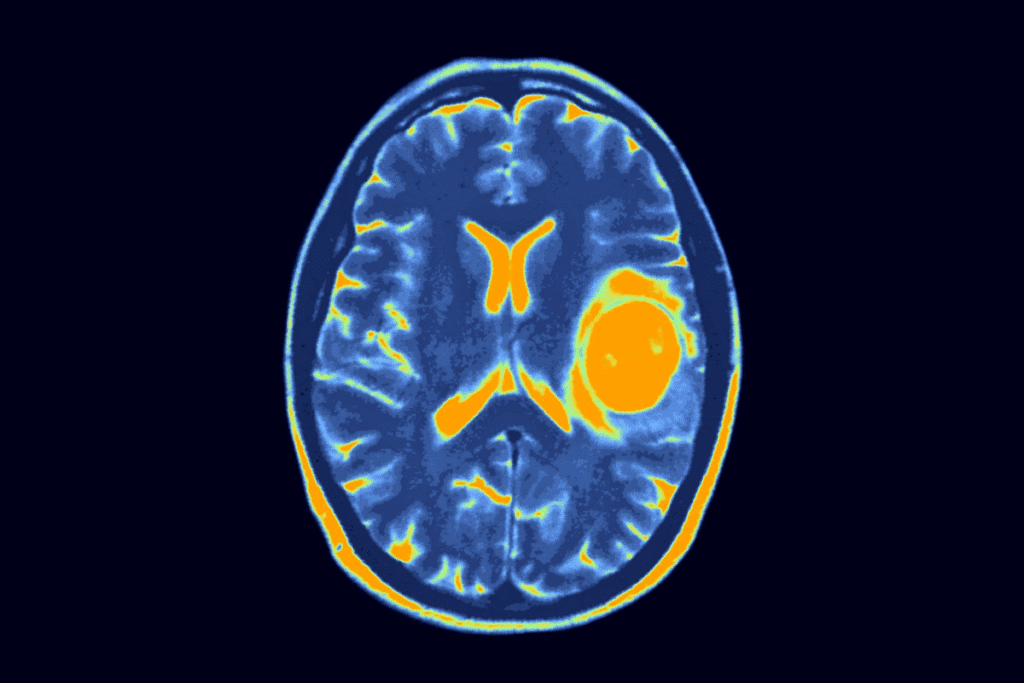

Imaging Studies

Imaging is key in finding pediatric brain tumors. We use MRI (Magnetic Resonance Imaging) and CT (Computed Tomography) scans